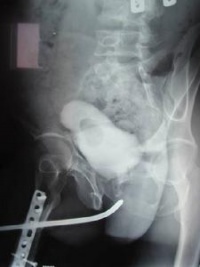

膀胱尿道造影尤适用于狭窄段口经细小或不能通过尿道探杆的病例。逆行尿道造影是由尿道外口边注入造影剂边摄侧位片,此时显示狭窄段远端较清楚。造影剂注入膀胱后,让病人一边解尿一边摄尿道侧位片(即顺行膀胱尿道造影),能较清楚地显示狭窄段近端。如患者已作膀胱造口术,可由造瘘管注入造影剂,然后在患者排尿时摄尿道侧位片。膀胱尿道造影尚可鉴别痉挛性还是器质性尿道狭窄,并可显示尿瘘。经尿道镜可以从尿道内观察到狭窄段的远端情况。

5.尿道造影:确定部位、程度、长度。

据了解,手术从前天上午8点半正式开始,由泌尿外科主任导师何恢绪亲自主刀。先通过膀胱找到尿道内口,在后尿道找到一狭窄部位,专家称这就是患者排尿困难的原因。原来车祸致尿道断裂后,在后尿道形成了一块2厘米厚的疤痕,致使患者尿道狭窄,排尿困难。手术持续了3个小时,何恢绪主任表示,手术很顺利,正常情况下阿章将在3周内可以康复出院。